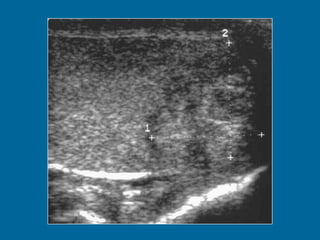

LINFOMA MALIGNO 1 a 8 % de los tumores testiculares. Pico de incidencia entre los 50 y 60 años de edad. Tumor testicular bilateral más común, sincrónico o metacrónico. 10% localizado al momento del diagnóstico (muy mal pronóstico). Ecografía Ecoestructura homogénea o heterogénea. Hipoecogenicidad. Degeneración hemorrágica y necrosis (raro). Afectación difusa con agrandamiento testicular. Nódulo o masa.

Transverse US image of the left testis shows multiple hypoechoic lesions.

LINFOMA MALIGNO 1a 8 % de los tumores testiculares. Pico de incidencia entre los 50 y 60 años de edad. Tumor testicular bilateral más común, sincrónico o metacrónico. 10% localizado al momento del diagnóstico (muy mal pronóstico). Ecografía Ecoestructura homogénea o heterogénea. Hipoecogenicidad. Degeneración hemorrágica y necrosis (raro). Afectación difusa con agrandamiento testicular. Nódulo o masa.

Transverse US imageof the left testis shows multiple hypoechoic lesions.